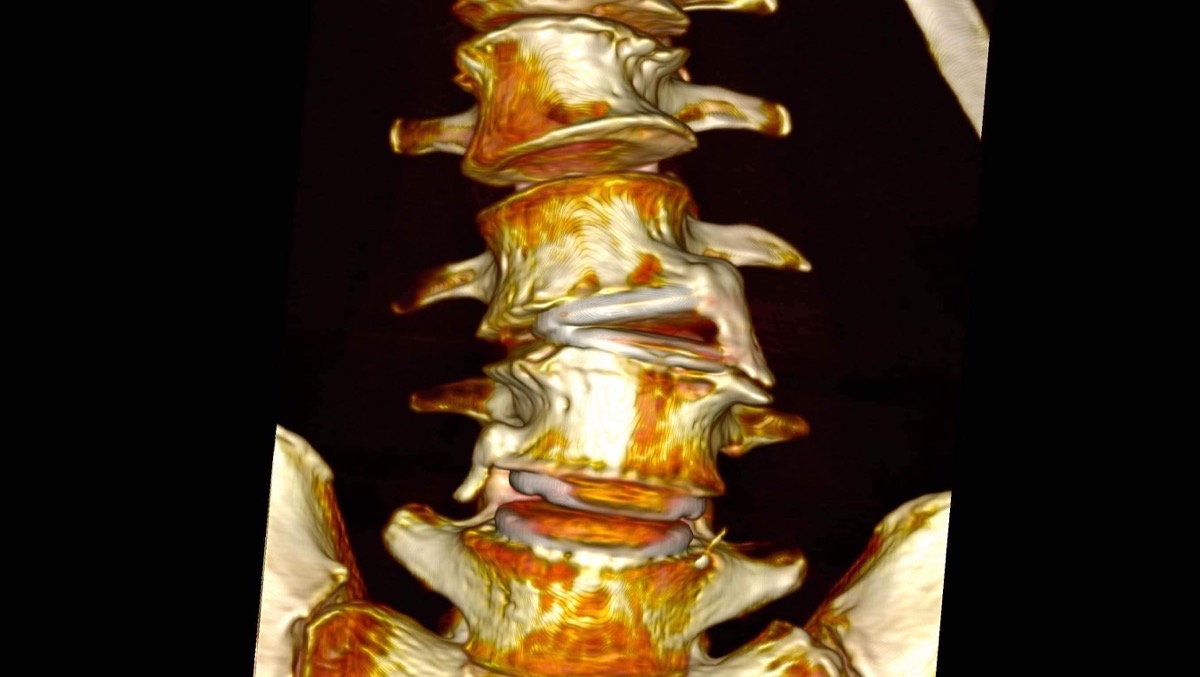

This is a 3D image of my Lumbar Spine with failed medical L-M6 devices (Artificial discs at the Lumbar L3/L4 & L4/L5 Levels).

Surgical Plan: 3 surgical stages to safely repair the damaged spinal levels.Dr. John Aschar, MD, orthopedic surgeon, of the Cantor Medical Institute, will repair the lumbar spine at the L3-L4 & L4-L5 levels, straighten my low back, and decompress the lumbar nerve roots.